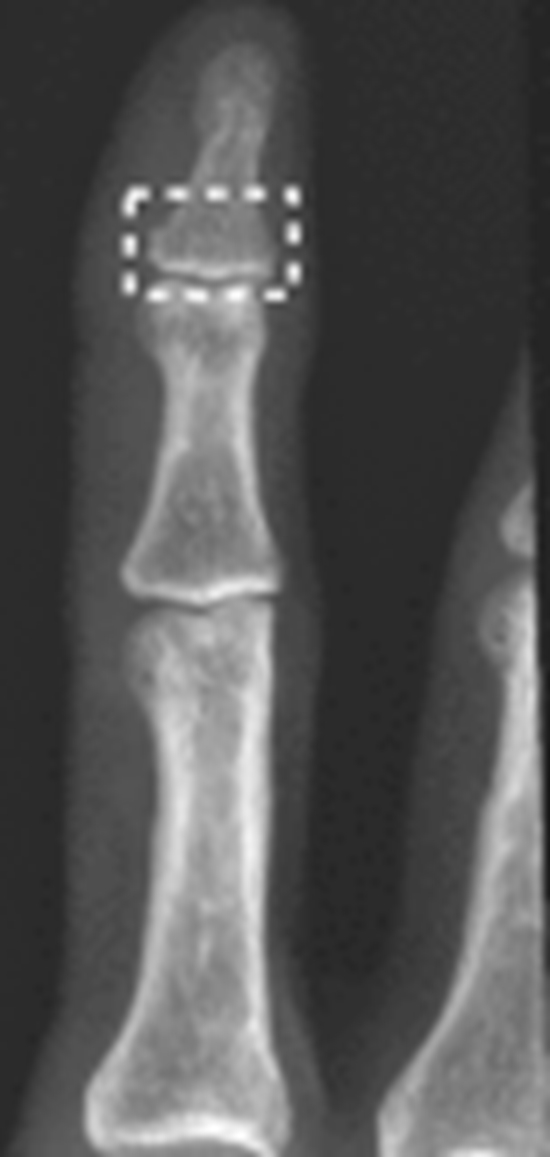

Accurate image interpretation is essential in the field of radiology to the healthcare team in order to provide optimal patient care. This article discusses the use of artificial intelligence (AI) confidence levels to enhance the accuracy and dependability of its radiological diagnoses. The current advances in AI technologies have changed how radiologists and clinicians make the diagnoses of pathological conditions such as aneurysms, hemorrhages, pneumothorax, pneumoperitoneum, and particularly fractures. To enhance the utility of these AI models, radiologists need a more comprehensive understanding of the model's levels of confidence and certainty behind the results they produce. This allows radiologists to make more informed decisions that have the potential to drastically change a patient's clinical management. Several AI models, especially those utilizing deep learning models (DL) with convolutional neural networks (CNNs), have demonstrated significant potential in identifying subtle findings in medical imaging that are often missed by radiologists. It is necessary to create standardized levels of confidence metrics in order for AI systems to be relevant and reliable in the clinical setting. Incorporating AI into clinical practice does have certain obstacles like the need for clinical validation, concerns regarding the interpretability of AI system results, and addressing confusion and misunderstandings within the medical community. This study emphasizes the importance of AI systems to clearly convey their level of confidence in radiological diagnosis. This paper highlights the importance of conducting research to establish AI confidence level metrics that are limited to a specific anatomical region or lesion type. KEY POINT OF THE VIEW: Accurate fracture diagnosis relies on radiologic certainty, where Artificial intelligence (AI), especially convolutional neural networks (CNNs) and deep learning (DL), shows promise in enhancing X-ray interpretation amidst a shortage of radiologists. Overcoming integration challenges through improved AI interpretability and education is crucial for widespread acceptance and better patient outcomes.